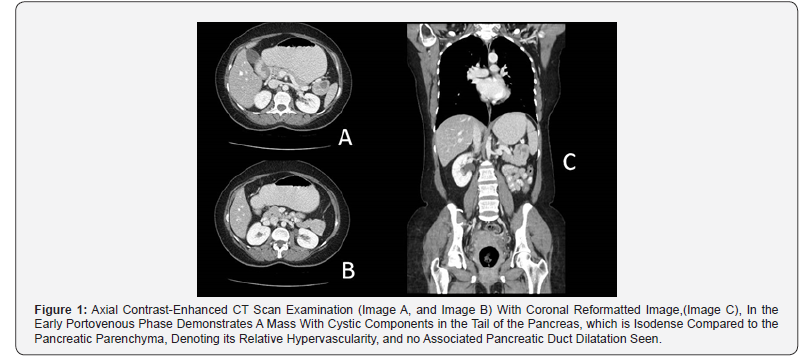

Since the management of anti-GAD cerebellar ataxia is case based and there are no clear treatment guidelines [4], we started a trail of triple maintenance therapy, after tapering the initial steroid therapy, which resulted in a significant clinical response. A course of monthly 25 grams IV immunoglobulin and 1000 mg Rituximab given at day1 and day 15 with a daily dose of 50 mg Azathioprine, for 2 weeks, then increased to 100mg for another 2 weeks, followed by a fixed daily dose of 150mg. After 6 months of initiating the treatment, the patient showed significant improvement in symptoms. She recovered from vertigo, nausea and vomiting, had considerable improvement in gait, as she could walk independently using walking aid occasionally. However, mild blurred vision and mild bilateral nystagmus persisted. The patient continued treatment with this clinically significant moderate improvement. However, a follow up of her anti-GAD Abs titer after 1 year of treatment was still persistently high, > 2000 U/mL, regardless of the remarkable clinical improvements, therefore, a second CT abdomen was done and showed 4.5 cmenhancing lobulated mass with internal cystic component at the pancreatic tail with no lymphadenopathy and no evidence of metastatic lesions (Figure 1). Thus, the patient underwent open distal pancreatectomy and splenectomy. Histopathological report showed neuroendocrine tumor grade II (Figure 2). The patient was discontinued from medical treatment and she recovered well from the surgery. There was dramatic added symptomatic and clinical improvement to her residual cerebellar symptoms